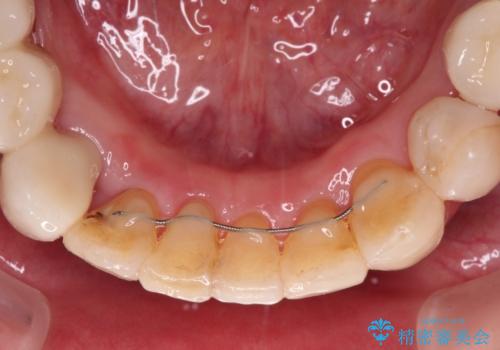

- 歯並びやグラグラする奥歯など、気になる所を全部治したいとのことで来院された患者様です。

奥歯は咬み合わせや歯周病により歯槽骨が失われていたり、むし歯や破折している歯などがあったりと、歯周病治療やインプラント補綴、矯正治療など、総合的に治療が必要と診断されました。

まずは歯周病治療やインプラント埋入を行い、環境が整った後にワイヤーを併用したインビザライン矯正を行い、オールセラミッククラウンにて補綴治療を行うこととしました。